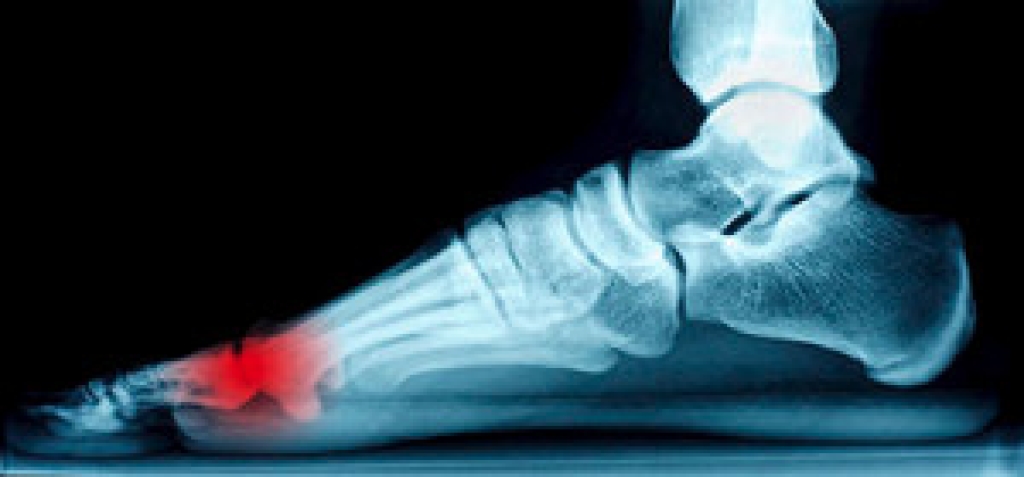

Causes of Heel Pain

Heel pain can be debilitating and can form due to a variety of reasons. The most common cause of heel pain occurs when the band of tissue that connects the heel bone to the toes, known as the plantar fascia, becomes inflamed causing plantar fasciitis. When the Achilles tendon becomes inflamed Achilles tendonitis may occur, and this can lead to heel pain too. Heel pain can also be caused by a natural wearing of the fat pad which is connected to the heel, as well as stress fractures, bursitis, or a variety of diseases such as arthritis and gout. If you are suffering from heel pain it is highly recommended that you visit a podiatrist who can determine what the cause of your pain is. A podiatrist will be able to provide a proper treatment plan for your heel pain as well.

Heel pain is often associated with plantar fasciitis. The plantar fascia is a band of tissues that extends along the bottom of the foot. A rip or tear in this ligament can cause inflammation of the tissue.

Achilles tendonitis is another cause of heel pain. Inflammation of the Achilles tendon will cause pain from fractures and muscle tearing. Lack of flexibility is also another symptom.

Heel spurs are another cause of pain. When the tissues of the plantar fascia undergo a great deal of stress, it can lead to ligament separation from the heel bone, causing heel spurs.